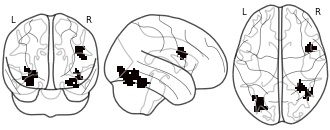

"name": "VBM_HeterogeneityMap",

"description": "Abnormal gray matter in BPD. Brain regions with significant heterogeneity (i.e. between-study variance) in the comparison of patients with BPD and healthy controls. Results are thresholded at at p<.005 & k>20. Note: Results are based on meta-analysis of group comparisons. Note2: Results were updated (see Erratum for this publication)",

"add_date": "2016-01-21T18:23:32.131003+01:00",